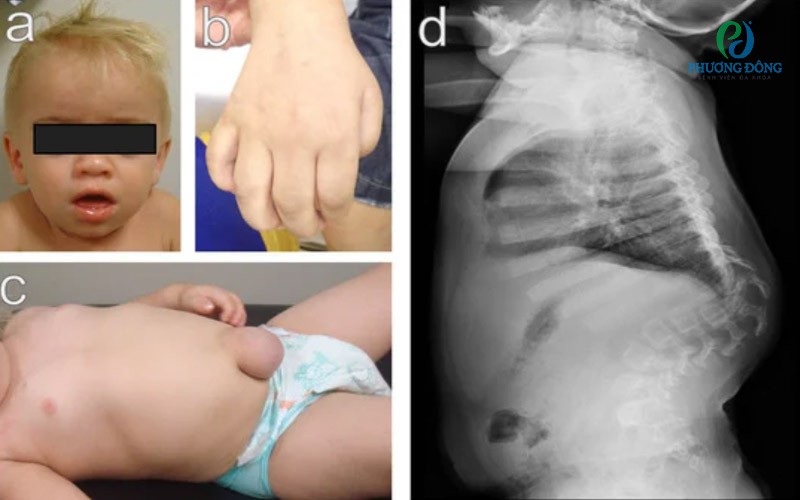

Các đặc điểm của hội chứng Hurler. Các đặc điểm của hội chứng Hurler.

Ghi chú:

• (a). Các đặc điểm khuôn mặt thô. Lưu ý trán rộng, cổ ngắn, đầu mũi rộng, các đặc điểm khuôn mặt thô và đục giác mạc.

• (b). Bàn tay vuốt do ngón tay bị cong vẹo.

• (c). Thoát vị rốn.

• (d). Nhìn nghiêng cột sống. Lưu ý gù cột sống ngực-thắt lưng và xương sườn rộng. Đã có sự đồng ý của bệnh nhân cho việc sử dụng hình ảnh.